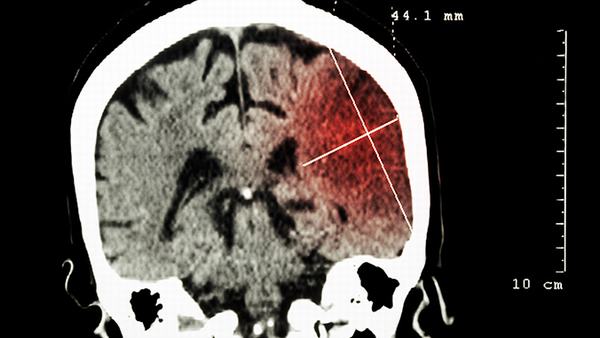

其次,老年脑萎缩主要表现为脑容量减小,大脑皮质变薄,并伴随着与认知相关的问题,如记忆力下降、思维迟钝等。小脑萎缩主要影响小脑,导致小脑体积缩小,进而影响身体运动和平衡控制。患者可能会出现手臂和腿部肌肉无力、协调障碍、共济失调等症状。

综上所述,老年脑萎缩和小脑萎缩是不同类型的脑部退化疾病。老年脑萎缩主要表现为大脑的退化和与认知有关的问题,而小脑萎缩则主要影响小脑,导致运动和平衡控制异常。虽然二者有一些相似之处,但由于发病原因、症状表现和治疗方法不同,需要根据具体情况进行正确的诊断和治疗。